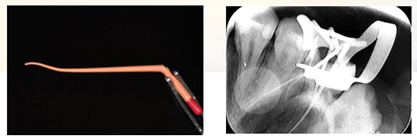

X-ray示:26远中低密度影已穿通髓腔,与近中低密度影几近相连。根尖无低密度影像。

复诊,无不适,去除冠部暂封,试主牙胶尖,拍摄X-ray。

iROOT SP糊剂单尖法根充四根管,SDR树脂髓腔充填,拍摄X-ray,显示根管充填完好。

小编觉得,一个根管治疗案例的成功前提在于,医生在治疗能够通过影像更好地判断病情和制作治疗方案。而从以上的案例中发现,孙老师在治疗过程中多次使用到了X-ray拍摄口内影像。而在口腔界中,X-ray影像已经逐步被数字口内影像板扫描处理系统成像所替代。

在治疗处理之前,可以通过术前X光片影像为后续治疗计划提供影像和数据的支撑,大大提高了治疗的成功和降低了治疗的风险。